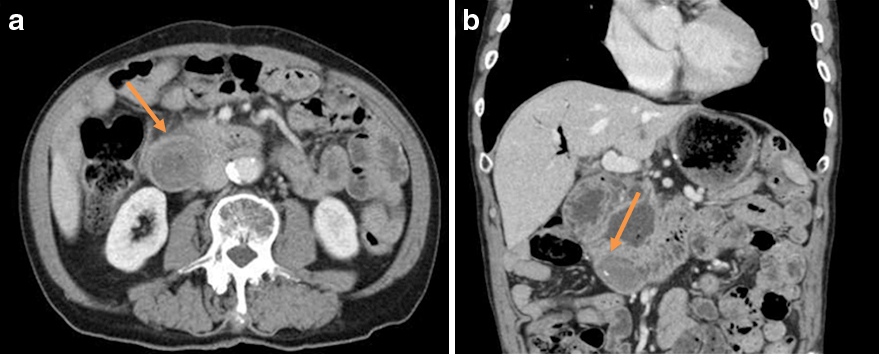

腹部造影CT所見:十二指腸内にやや低吸収の類円形の構造物を認めた(Fig. 2a, b).また,冠状断で傍乳頭憩室の軽度の拡張を認めた.しかし,その盲端側の拡張などは認めず,膵周囲の脂肪織濃度の上昇なども認めなかった.

Abdominal enhanced CT revealed a round structure at the site of the Roux-en-Y anastomosis (orange arrows) (a, b).